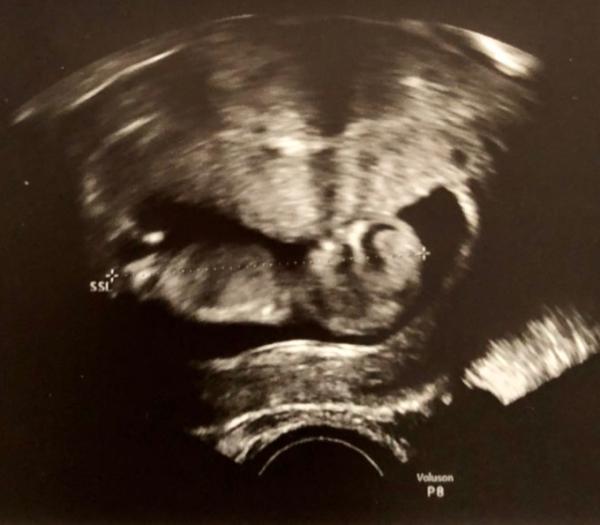

Hallo zusammen, wir waren letzten Mittwoch zum ersten richtigen Ultraschall Alles ist super, mein ET wurde jetzt festgelegt und sogar eine Woche vorgezogen (also ursprünglich hab ich ja immer von der letzten Periode gerechnet). Mein ET ist jetzt der 19.04., SSL lag bei 5,6cm und die Nackenfalte sah unauffällig aus. Und diesmal habe ich eine Hinterwandplazenta, bei den letzten beiden Schwangerschaften hatte ich eine Vorderwandplazenta.

Bild zu Bericht vom Frauenarzt - Forum für April - Mamis